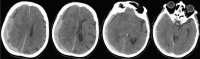

Das akute Subduralhämatom bei geriatrischen Patienten: Wieviel Neurochirurgie brauchen wir? // The role of age in the treatment of traumatic brain injury

Journal für Neurologie, Neurochirurgie und Psychiatrie 2018; 19 (2): 53-58 Volltext (PDF) Summary Praxisrelevanz Abbildungen